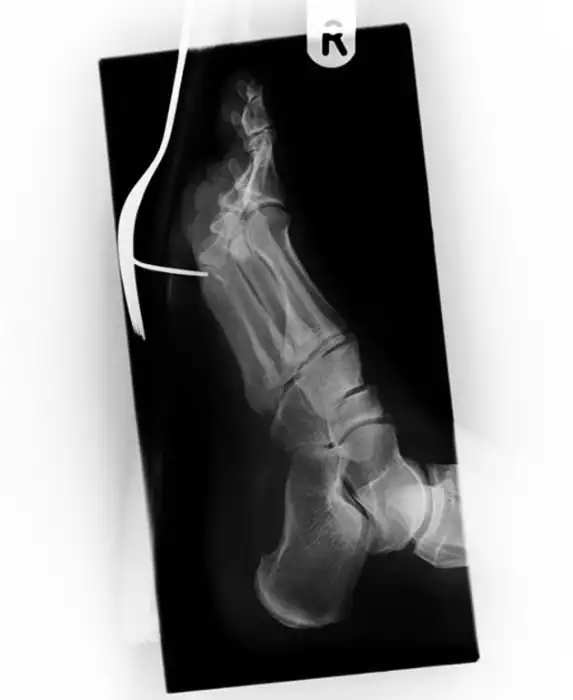

Жуткие рентгеновские снимки

Порой даже не верится, с какими странными и необычными повреждениями в травматологию могут поступить пострадавшие. Всю эпичность профессии врачей травматологии могут с легкостью подтвердить рентгеновские снимки.